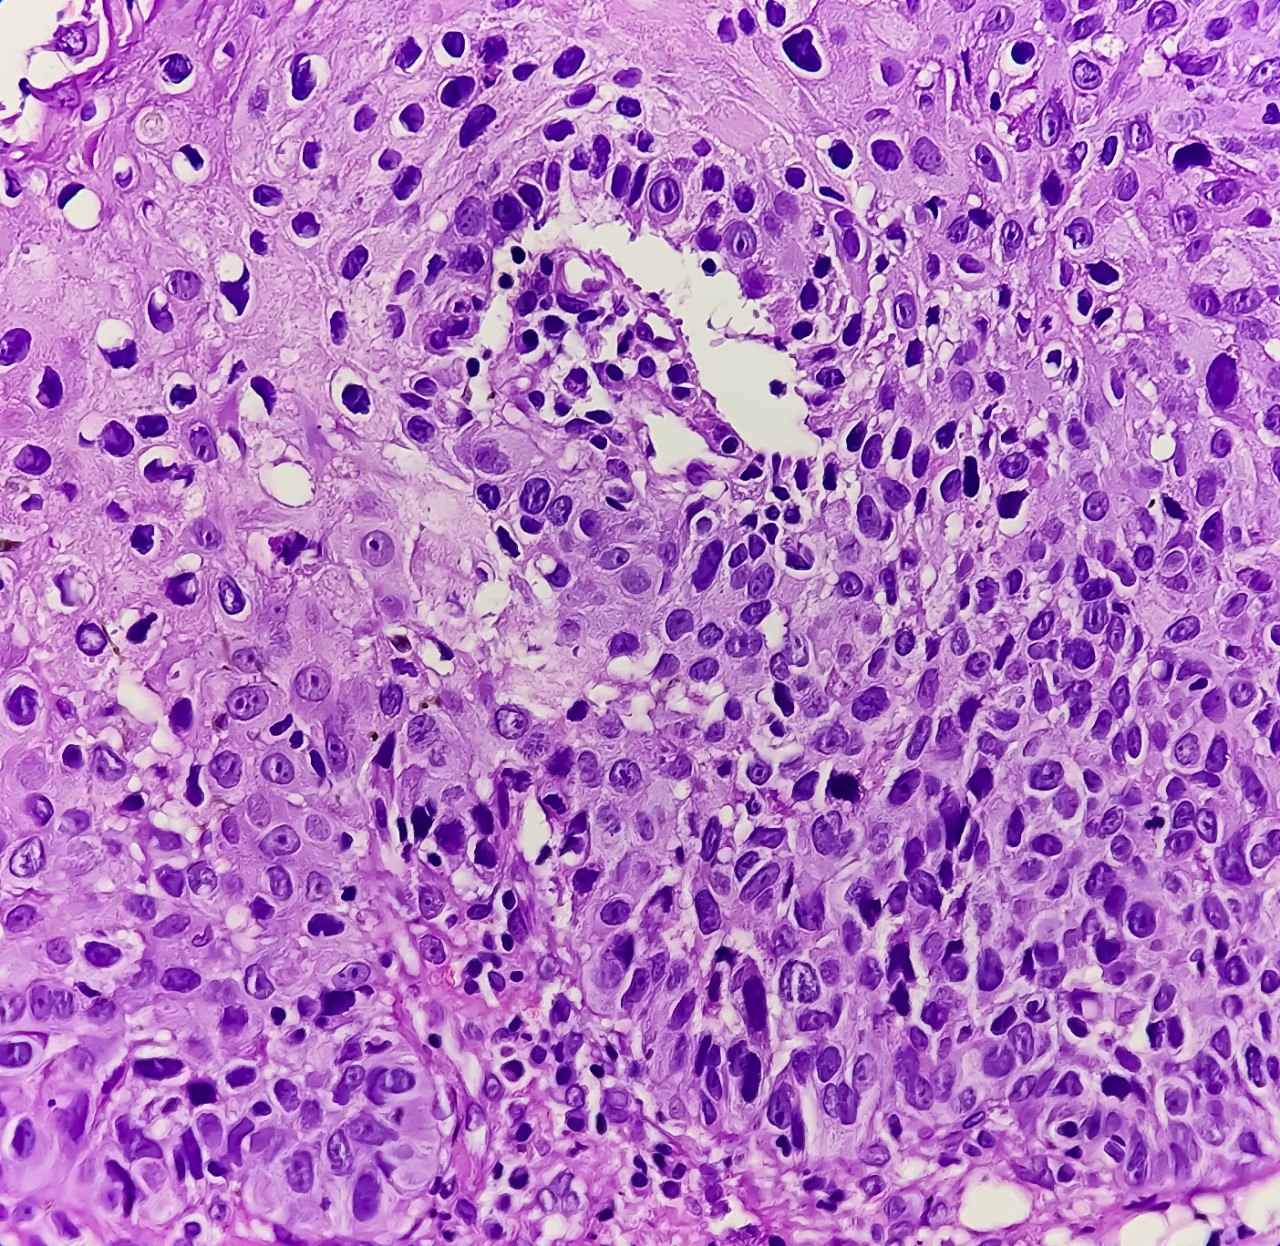

Featured photo at top of oropharyngeal cancer cells stained purple. Photo/Md Babul Hosen/iStock Photo.